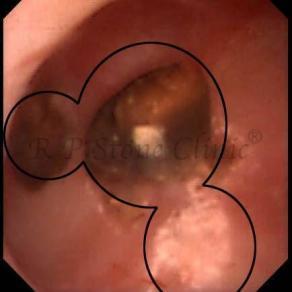

Kidney stone is a solid mass of CRYSTALS. It is the process of crystallization which initiates the formation of kidney stones. This happens in nephrons or units of kidney. Once a small crystal is formed, it can both grow & unite with other crystals leading to the formation of small concretion which eventually forms a stone. Once these large crystals detach from the collecting ducts, the process of stone formation starts in the renal collecting system. A recurrent kidney stone former is advised to know a little bit about something known as Randall’s plaque. Alexander Randall discovered plaques on the renal papillae eight decades back based on examination of 1154 pairs of autopsied Kidneys. He described these renal papillary lesions as cream colored or milk patch areas composed of calcium phosphate & calcium carbonate. These plaques could act as NIDUS for formation of KIDNEY STONE. Calcium Oxalate stone can form on this nidus & then detaches from this plaque to become a free floating stone in the collecting system of kidney

These images are taken as snap shots from the video recording of RIRS Surgery done at our hospital. These are Randall’s Plaques seen with Digital FLEX XC & Digital FLEX XC S. The cream or whitish patches are seen on the tips of RENAL PAPILLAE as seen in images below.

Randall’s Plaques may lead to the formation of Stones.

Those kidney stone patients who have Randall’s Plaques in their kidneys are more likely to form stones again (Recurrent Stones).

Stone Patients in whom Randall’s Plaques are detected at the time of RIRS Surgery should undergo regular ultrasound examination for early detection of stones.

Patients of Stones with Randall’s Plaques in their Kidneys should drink plenty of fluids in addition to Orange Juice & Lemonade.